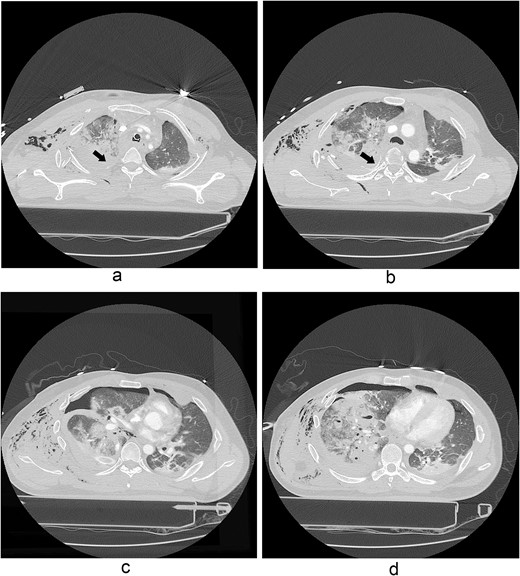

The thoracotomy incision was relatively small, ~8 cm in size, and the intercostal space was not spread to prevent further intraoperative chest wall damage. There were multiple lung lacerations in the upper, middle, and lower lobes with active bleeding. Bloody leakage continued through the avulsed parietal pleura and mediastinum. Hemostasis was achieved by suturing the deeply lacerated lung and packing with gauze (Combat Gauze ™ [Z-Medica QuikClot]) at the chest wall and mediastinum. The operation took 130 minutes. The transfusion of plasma, platelets, and red blood cells was balanced according to the following quantities: 10, 10, and 14 U, respectively. After surgery, the patient was transferred to the intensive care unit (ICU). The PaO2/FiO2 ratio was 52 mmHg with a Positive end expiratory pressure of 15 cm H2O, at a peak inspiration pressure of 30 cmH2O. ABGA showed pH 7.23, pCO2 42, and pO2 47. Veno-venous ECMO based on bilateral femoral vein cannulation was performed (Fig. 3a). Considering the patient’s hemorrhagic predisposition, heparin was not used. Disseminated intravascular coagulation (DIC) occurred along with acute renal failure. Antithrombin III infusion and continuous renal replacement therapy (CRRT) were initiated on the second hospital day. By the 5th day, oxygenation was achieved without ECMO support, followed by decannulation. On the 6th day, the second operation was performed in about 35 minutes. The gauze was removed, and no active bleeding or oozing was seen (Fig. 3b). The third operation, performed on the 13th day, was an open reduction of right ribs 3–7 for correction of flail chest and took 75 minutes (Fig. 3c). After open reduction, the flail chest improved, but the patient was not able to be weaned off the ventilator. Pneumonia and bacteremia developed. A tracheostomy was performed on the 15th day. CRRT was switched to hemodialysis, which was stopped on Day 28. The patient was discharged on the 47th day without tracheostomy. Ten months postoperatively, pulmonary function testing revealed forced expiratory volume in one second and diffusion capacity of carbon monoxide of 77% and 67% of predicted values, respectively. The chest CT and radiographs showed that the lungs had healed well, and there was no displacement of the ribs (Fig. 4). The patient recovered and returned to work.

Chest radiograph and CT scan 10 months after the accident. (a) Chest radiograph showed well-healed fractured ribs and expanded lungs without active lesions. (b)–(e) Non-enhanced axial chest CT images showed recovery from injury.